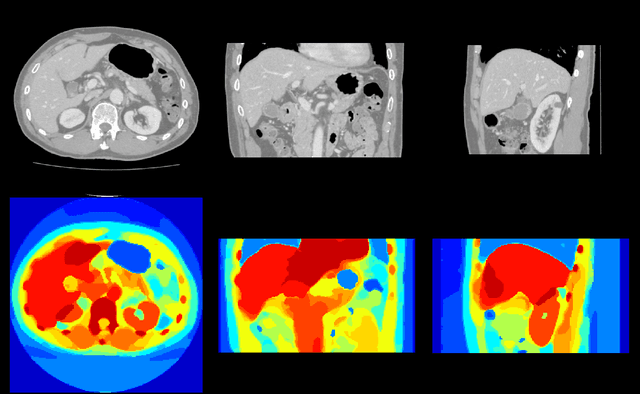

To efficiently establish training databases for machine learning methods, collaborative and crowdsourcing platforms have been investigated to collectively tackle the annotation effort. However, when this concept is ported to the medical imaging domain, reading expertise will have a direct impact on the annotation accuracy. In this study, we examine the impact of expertise and the amount of available annotations on the accuracy outcome of a liver segmentation problem in an abdominal computed tomography (CT) image database. In controlled experiments, we study this impact for different types of weak annotations. To address the decrease in accuracy associated with lower expertise, we propose a method for outlier correction making use of a weakly labelled atlas. Using this approach, we demonstrate that weak annotations subject to high error rates can achieve a similarly high accuracy as state-of-the-art multi-atlas segmentation approaches relying on a large amount of expert manual segmentations. Annotations of this nature can realistically be obtained from a non-expert crowd and can potentially enable crowdsourcing of weak annotation tasks for medical image analysis.